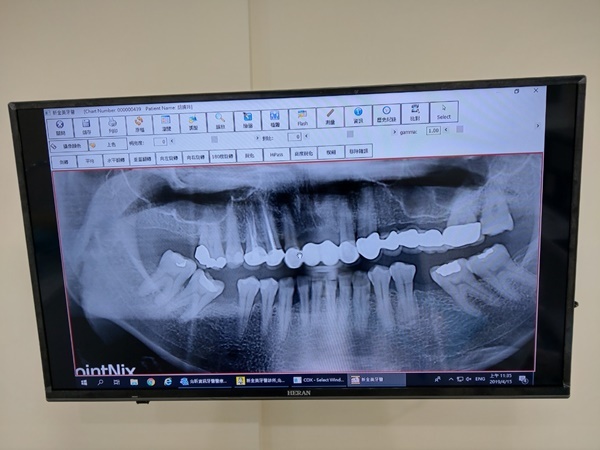

過程中,楊策淳醫師也很用心,非常小心的幫妹妹先洗牙,然後待會植牙手術會進行多久,甚麼都有說,讓我們姊妹倆放心不少,而且小護士也是很輕聲細語的引導妹妹,過程中看妹妹舒服成這樣,我也就沒多看了(其實是有點怕血哈哈),但大家不用怕會失血過多喔!楊醫師這邊一定會在第一次諮詢時就評估患者身體狀況,然後讓患者自己考慮要不要來植牙,來回溝通確定好再來第二次看診就可以植牙了~所以建議大家可以先來這邊諮詢,不會花大家太多錢跟時間,只有基本掛號費也能問到想知道的療程喔!而且牙醫診所植牙費用很實在不會亂報價,在台中植牙便宜沒幾間,若貪植牙費用便宜後面問題一堆未來才更傷荷包。

後來貼心小護士走來告訴我妹妹快好了,讓我去看看我一進去雖然差點嚇死…可是為了幫妹妹紀錄,我還是勇敢的拍下這張(死小瑜妳欠我一次…),為了不造成大家看文暈倒情況,我碼到剩縫線了…大致上就是把妳的牙肉切開就是傳說中翻瓣植牙手術,然後把植體種進去,在把傷口縫起來。怕了嗎…?告誡大家除了無法預知意外,不然一定要顧好牙齒啊…

說實在我也不好受,植牙是需要恢復期三到六個月,尤其是上面牙齒,恢復期會比下面長一點,至少六個月以上,主要是因為上排骨頭比起下排牙骨還來的薄,恢復後還要再來回診一兩次,最後完全癒合才會給正式假牙,戴習慣之後醫師就會幫患者固定,才有大家現在看起來這麼自然健康的牙齒。剛植完植體還是要好好保養喔,聽楊醫師說如果植牙後回去沒有好好保養,中途可是很容易發炎,到時候就要再次回診去給醫師檢查,嚴重可能要再清除一次,所以來植牙的各位無論是微創植牙、翻瓣植牙,也一定要繼續保養口腔,不然會很可怕。